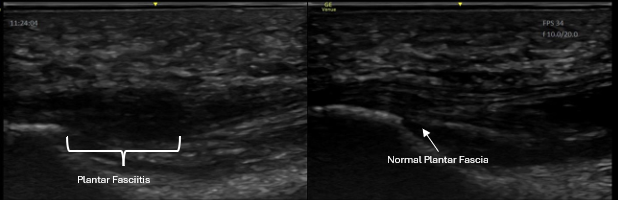

Diagnostic ultrasound is especially useful for common injuries seen in active adults and athletes, including:

• Achilles & ankle injuries

• Compare injured vs non-injured side in real time